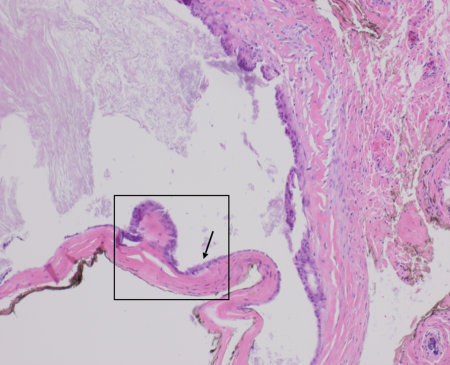

Microscopically, apocrine hidrocystomas can appear as a unilocular or multilocular cystic lesion composed of two layers. The first layer is the inner cyst wall that is composed of secretory columnar epithelium. The secretory columnar epithelium can consist of a single layer or a double layer of cuboidal-columnar epithelium. [6] The inner layer of the cysts lies in front of the myoepithelial cells which comprise the outer or peripheral layer. [7] When lipofuscin granules are present, PAS-positive granules can also be seen histologically.[1] Apocrine hidrocystomas also exhibit papillary projections which appear in the lumen of the cyst as an outgrowth from the wall. Papillary projections consist of vascular connective tissue covered by secretory epithelium. [7]